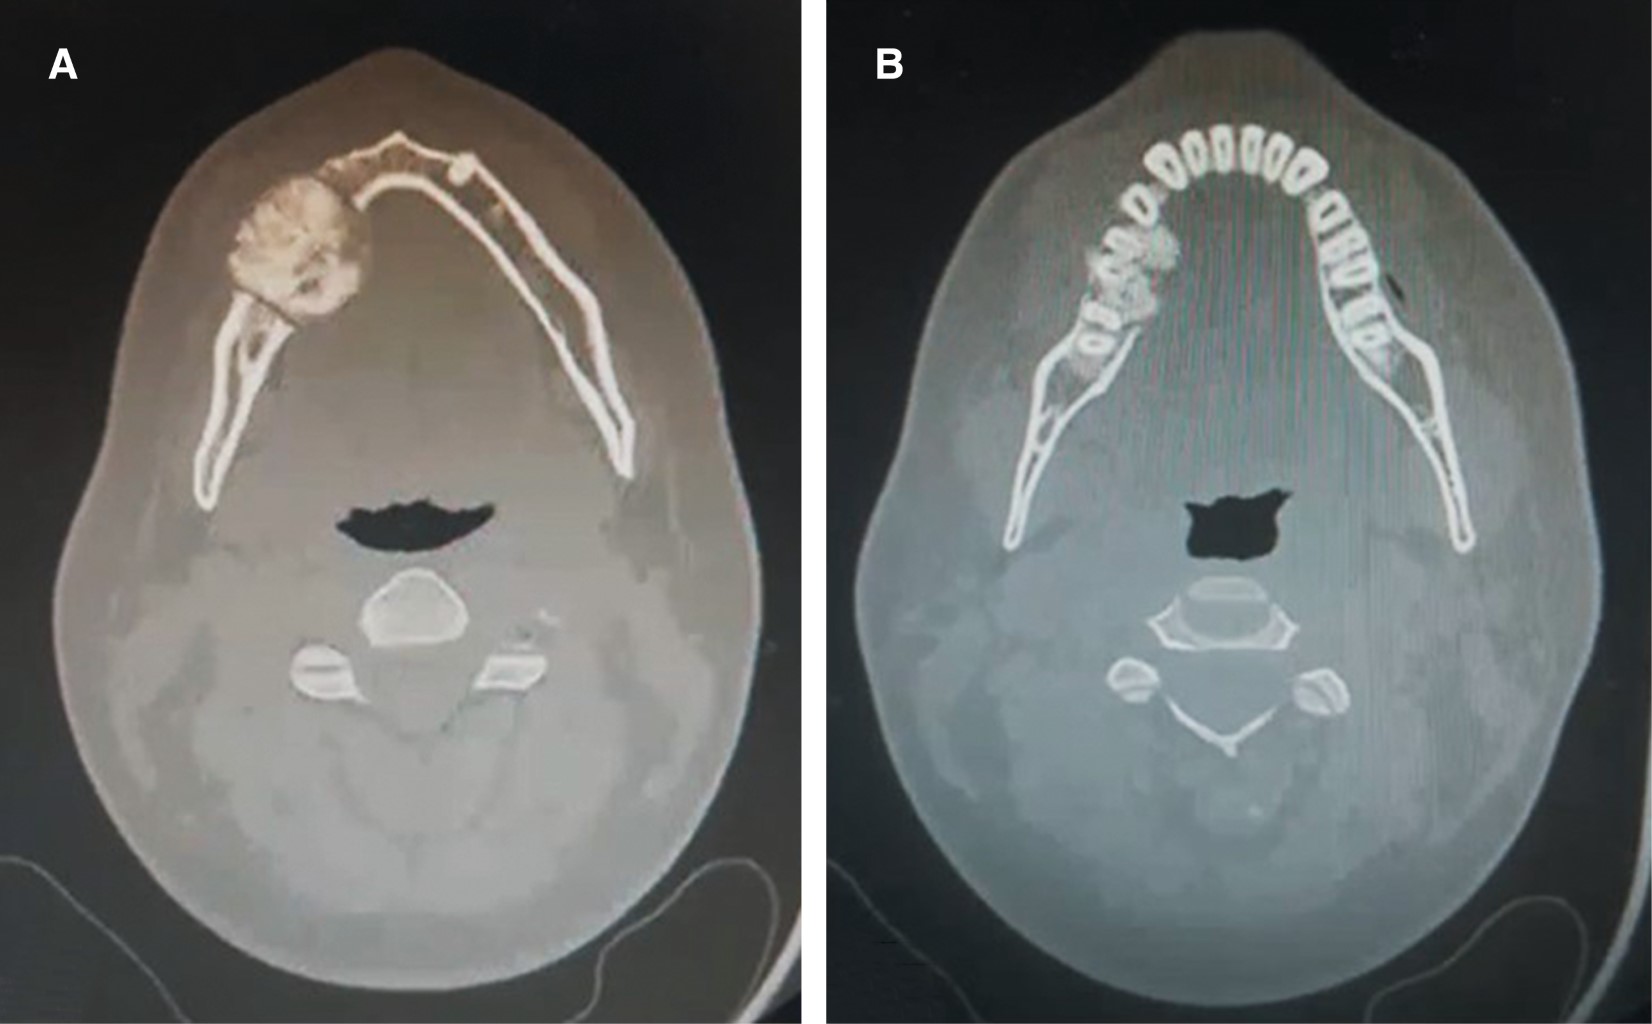

Cementoblastoma - Wikipedia Apical Radiopacities - Radiodontics Cementoblastoma: Features, Diagnosis, and Treatment Cementoblastoma. Classic appearance of a sclerotic tumor fused ... ❇ Benign Cementoblastoma Radiology: ▶ Location: → 78% in ... Cementoblastoma